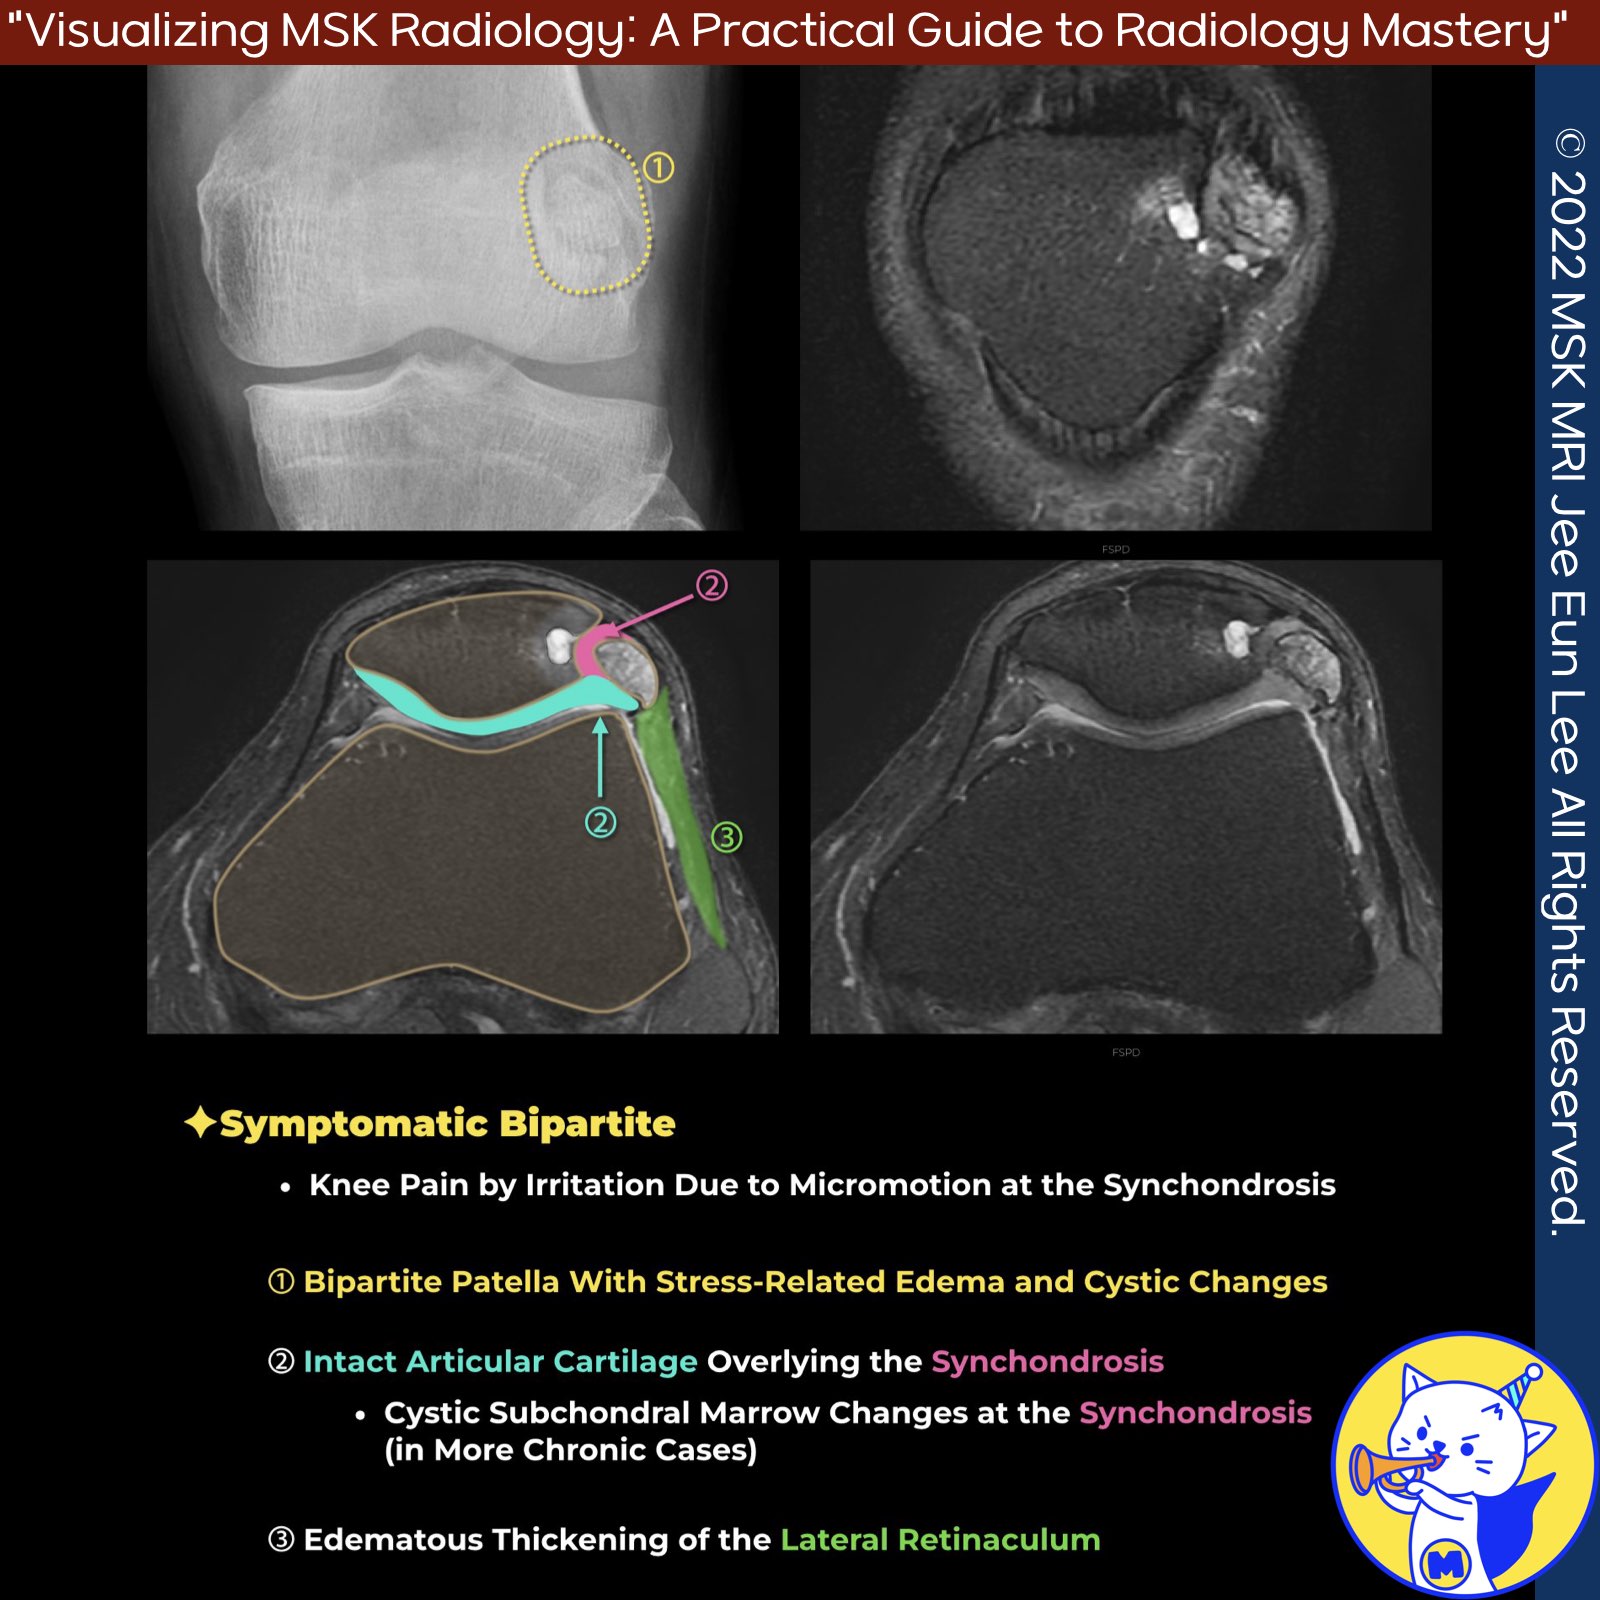

📌 Symptomatic Bipartite or Multipartite Patella

✅ MRI Findings:

- Edema in the bipartite fragment

- Fluid signal at the synchondrosis, suggesting pseudarthrosis

- Cystic subchondral marrow changes at the synchondrosis in chronic cases

- Fluid signal may be seen between the fragment and the patella

✅ Cartilage Involvement:

- Articular cartilage overlying the synchondrosis typically remains intact, even in advanced disease

✅ Treatment:

- Surgical excision or lateral retinacular release for symptomatic bipartite patella